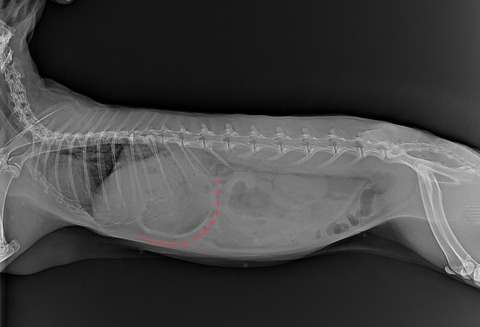

診断は触診、レントゲンで行います

胃は正常であれば、最後肋骨を少し越えるか越えないかくらいの大きさです

(⇩正常なサイズの胃)

胃拡張になると、最後肋骨を大きく越えてきます

(⇩急性胃拡張)